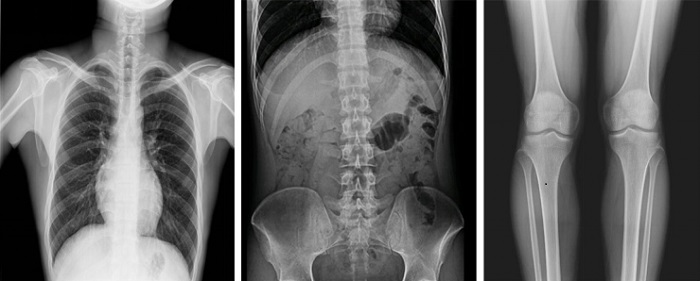

以普利德多功能動(dòng)態(tài)平板DRF為例,一改傳統(tǒng)DR只能進(jìn)行盲拍的模式,通過多角度動(dòng)態(tài)實(shí)時(shí)影像實(shí)現(xiàn)全方位觀察,當(dāng)疑似病灶出現(xiàn)時(shí),進(jìn)行瞬時(shí)高清點(diǎn)片,精準(zhǔn)捕獲高清病灶圖,大大降低漏診誤診率。同時(shí),17×17英寸大幅面成像,能對(duì)胸部、腹部等部位實(shí)現(xiàn)大范圍全覆蓋,更便于醫(yī)生觀察和診斷。